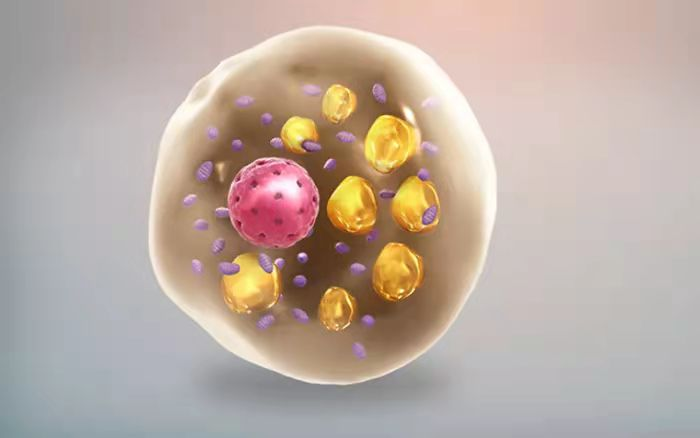

关注生物科学的读者朋友们可能知道,在人体内有两种形式的脂肪组织,一种是储存油脂的白色脂肪组织,脂肪细胞以单颗大油滴的形式储存能量,另一种褐色脂肪组织,细胞内有很多小颗粒油滴和线粒体,是燃脂运动中转化为热量的脂肪。而在这两者之间还有一种游离的“墙头草”脂肪细胞,是一些颜色较深的米色脂肪细胞,它们可以在一定条件下被激活,燃烧能量。

(褐色的脂肪细胞)

而新的治疗思路就是设法让脂肪细胞“褐化”,让它们多耗能、多产热。在这项研究中,科学家们发现,脂肪细胞的褐化有赖于它们制造并降解糖原的能力。具体来说,糖原的这种周转变化会驱动脂肪细胞持续表达一种叫做UCP1(解偶联蛋白1)的蛋白,这个信号告诉细胞,可以安全地“解偶联”ATP分子的生成,从而更快地燃烧能量。

根据这项新发现,针对一些肥胖人群,或许可以靶向脂肪细胞中的糖原代谢。无独有偶,前些日子中山大学医学院杨中汉教授的团队在PLOS Biology上发表最新论文,研究人员发现了促进脂肪燃烧的免疫分子。通过给小鼠注射刺激这种免疫分子后,它们即便大吃大喝也不会肥胖,还能保持代谢健康。而原理类似脂肪细胞的“褐化”,研究人员通过注射特定免疫系统信号分子刺激脂肪细胞,增加脂肪细胞中的“墙头草”米色细胞数量来调节代谢。米色的脂肪细胞中富含线粒体,而线粒体可以大量地消耗能量。